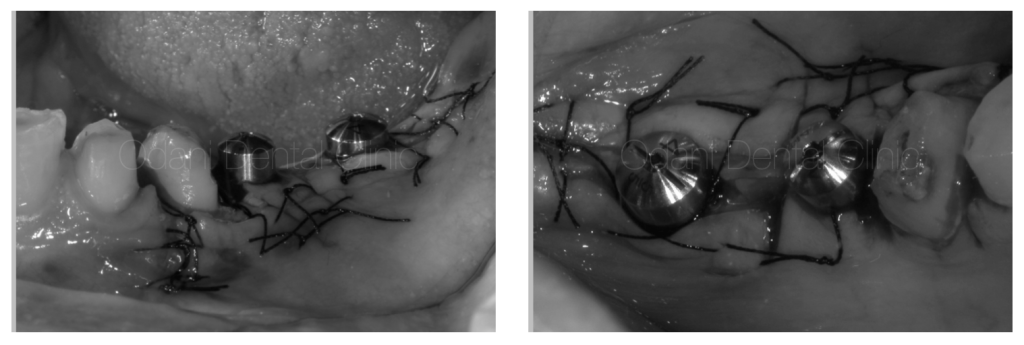

二次手術

インプラントが骨と結合したら、次に行うのは「頭出し」と言われる二次手術となります。頭出しを行うことで、治癒後にインプラントを支えとした歯を作製することが可能になります。

また、頭出しのタイミングは周囲の歯ぐきの状態を改善するチャンスでもあり、歯周病手術の技術を応用することが多いです。本症例においてはインプラント周囲の歯ぐきをさらに増やすようにズラして縫い合わせを行い、手前の歯との流れを整えて清掃しやすい環境作りに努めました。

二次手術治癒後の状態です。